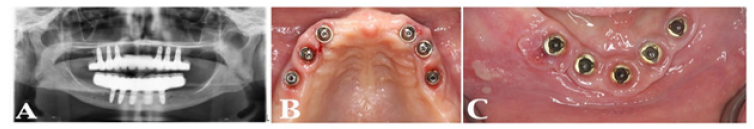

Osseo integrated implants are a safe and efficient treatment modality for dental and oral rehabilitation. One of the most common complications of endosseous implants is peri-implant inflammation, which is associated with the disturbance of the normal microbiome, affecting the soft and hard tissues surrounding the implants [26]. It clinically appears as an erythematous lesion with edema, occasionally ulcerated, sometimes painful, with bleeding and presence of an inflammatory exudate. OSCC with the erythroplakia appearance could be easily mistaken with peri-implantitis disease as it can mimic a benign inflammatory condition. A biopsy is highly recommended when conventional treatment fails to resolve the lesion or in some cases if its appearance is sudden and severe [27]. Although common sites for OSCC to develop are on the tongue, lips and floor of the mouth and around inflamed peri-implant area [28,29], the author has also seen a clinical case associated with mucosa around dental implants of a 68 years of age female restored with fixed implant Metal-acrylic resin (PMMA) prostheses FP3 [30], on both maxillary and mandibular arches (Figure 1 & 2), referred to practice for urgent consultation due to pain and discomfort of soft tissue around mandibular implants (Figure 3), upon suspicion patient was referred back to the treating dentist, in her hometown, and later pathology report confirmed OSCC diagnose (Figure 1-4).

Peri-implantitis is a risk factor for developing OSCC when it remains unresolvable. Implants’ long-term success and survival depend on the healthy soft tissue around implants (Figure 4); selecting the right patient, proper materials, treatment design, and post-treatment routine maintenance are crucial, as biofilm development and altering normal microbiota are inevitable.